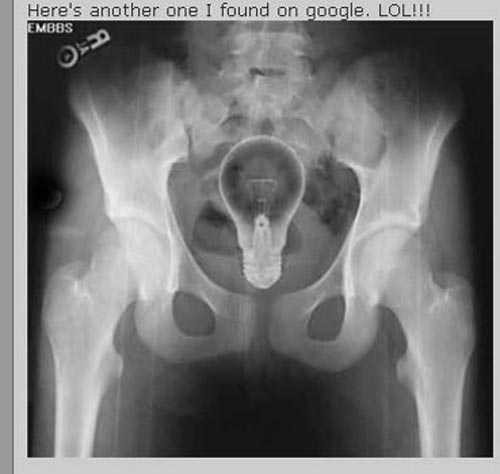

![]() |

| Bóng đèn vẫn nguyên vẹn bên trong người bệnh nhân |